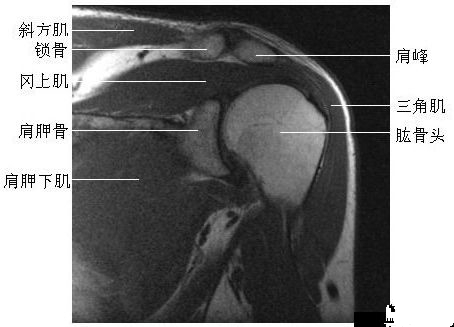

肩关节冠状面(二)